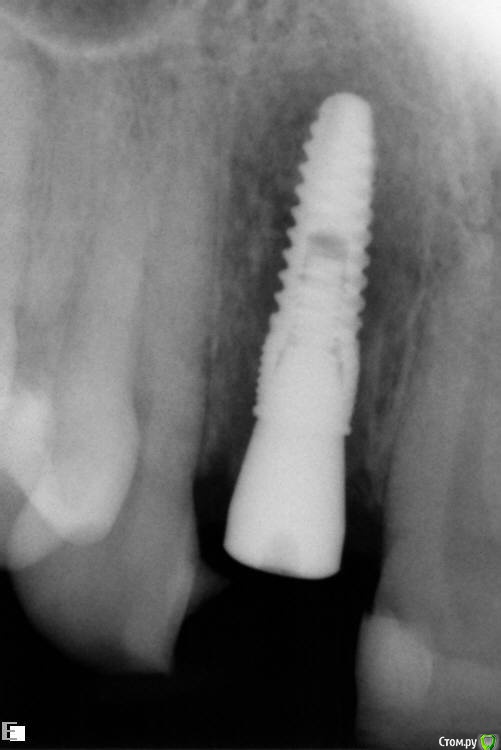

Slaggy Опубликовано 19 июля, 2016 Поделиться Опубликовано 19 июля, 2016 История -Корень 22 с выведением материала и периапикальным процессом - Удаление, кюретаж, обработка лазером, имплант+фдм и домик Нуф-Нуфа приклеенный к 21 и 23.Через 4 месяца выкрутился за формирователь. Куча грануляций, вестибулярное окно на уровне апикальной трети импланта маргинальный край кости сохранен.. Сделано -Кюретаж, Остеон2, пародонкол, ушито. Домик Нуф-Нуфа возведен вновь. По прошествии 2х месяцев -Пациент жалуется на увеличение пространства между понтиком и десной. Периодическое попадание крошек материала в полость рта. Слизистая малинового цвета. Отека нет. "Промывное пространство" увеличилось на 2 мм. В толще слизистой гранулы Остеона. Некоторые совсем у поверхности, можно ковырять зондиком..Боли или неприятных ощущение пациент не испытывает. Убирать все или подождать? Чего ждать от ситуации? Ссылка на комментарий

Slaggy Опубликовано 22 июля, 2016 Автор Поделиться Опубликовано 22 июля, 2016 Что за обработка лазером?Стерилизация лунки - Иногда лазером, иногда гексидином промываюЯ в это шаманство верю слабо, но "каждая мошка мяса - трошку" koreandrОтправлен 20 июля 2016 - 14:49Если выходит материал, значит есть откуда выходить. Дырка. Вот и вся биология. Через 2 месяца после операции дырок быть не должно в идеале. Вот и я о том - где мембран и периост? фоты нашел преоп и на момент фэйла снимок и фото Ссылка на комментарий

Slaggy Опубликовано 22 июля, 2016 Автор Поделиться Опубликовано 22 июля, 2016 Попробуй открыться конвертом и подшить туда лентой сст с бугра вертикально. Рост коллагена пойдёт на пользу. Кюретажить и сыпать ведь бестолку в такой ситуации. это старые фото на момент дезинтеграции имплантасейчас вестибулярно ушло и по высоте ушлофото нет назначил антибиотикичерез пару недель посмотрим, как события развиваются думаю за луночковый остеомиелит Ссылка на комментарий

Slaggy Опубликовано 15 августа, 2016 Автор Поделиться Опубликовано 15 августа, 2016 (изменено) Тут просили картинки-20/05,2016 , 15/08,2016 Графт продолжает всплывать через слизистую, хрустит при пальпации области аугментации Почистил слизистую от графта, дам паузу 2 недели и вычищаю все начисто. Изменено 15 августа, 2016 пользователем Slaggy Ссылка на комментарий